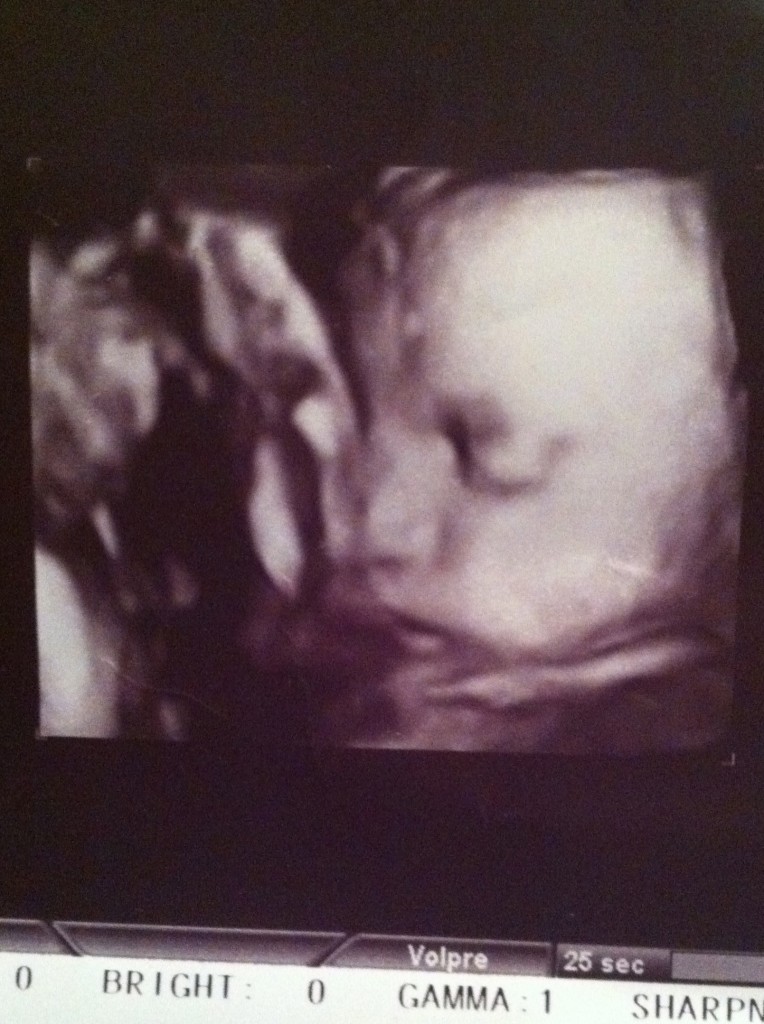

Skip ahead to now… we are just over 3o weeks. Our wonderful doctor moved clinics, and due to the exorbitant prices of the new clinic, we needed to find a new doctor. I saw one at our original clinic but she was just not the right fit for us. We made an appointment with Dr. Kong, who comes highly recommended from many friends here (she’s delivered just about every SCIS Pudong baby in the last 10+ years). We had our first appointment yesterday and LOVED her, our midwife, and the nurses. SO thankful, as changing doctors during our first pregnancy, in a foreign country, this late in the pregnancy was a fairly large source of stress. That stress melted away within minutes of walking into our appointment. As if loving our new caretakers wasn’t enough, we were treated to these INCREDIBLE 4D ultrasound photos of our Isla…

I cannot get over how beautiful she is! I love those chubby little cheeks already!!! My eyes welled with tears throughout the ultrasound… so, so thankful! Everything felt so much more real once we saw her little face. Our sonographer excitedly jumped up and down, announcing that Isla has lots of long hair! I couldn’t believe it. She focused on the top of her head and showed us the hair. Additionally, Isla is “head down” (hooray!), weighs 1.6kg, and right on track. Mommy, however, was diagnosed with gestational diabetes a few weeks earlier (boo!), but we suspect this is due to my indulgence of evil (but yummy) foods at home over the summer. Got my diabetes test and will now be monitoring my blood sugar 4 times a day. Not the most fun, but worth it to ensure our little pumpkin is healthy.